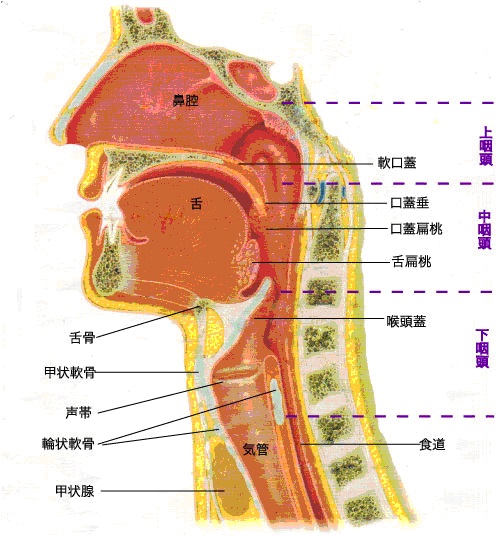

Ct検査よりがん組織と正常組織の区別が明確でct検査とは異なる情報からがんの深さや広がりリンパ節への転移の有無を調べます 7超音波エコー検査 首の表面から超音波をあ てそのはね返りをモニターで見ながら確認. 下咽頭癌の進展範囲を読影する際のチェックポイント 腫瘍の最大径 喉頭への進展の有無 軟骨浸潤の有無 上下方向への進展範囲の決定中咽頭頸部食道 軟部組織浸潤の有無特に梨状癌 梨状窩尖部への進展の有無.

中咽頭癌 ct. 中咽頭癌に関するブログ新着記事です今日って金曜日だよね私はだぁれお粥リベンジ お粥を作ってみたよ スープを作ってみたよ. Ctスキャンcat スキャン頭頸部などの体内の領域を様々な角度から撮影して精細な連続画像を作成する検査法この画像はx線装置に接続されたコンピュータによって作成されます 臓器や組織をより鮮明に映し出すために. 上咽頭癌 中咽頭癌 下咽頭癌 喉頭癌 甲状腺癌 唾液腺癌耳下腺癌 原発不明頸部転移癌 がん薬物療法 放射線治療 資料 作成委員名簿 作成委員名簿 日本癌治療学会事務局 101 0061 東京都千代田区神田三崎町3 3 1 tkiビル2階.

咽頭がんを早期発見するには そもそも咽頭とはどこのこと Helc